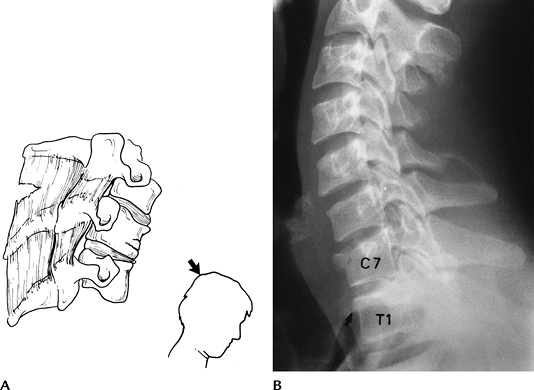

FIGURE 3-1 Disruptive hyperflexion injuries. (A) Mechanism (blow to the occipital region) that causes more posterior soft tissue injury compared with anterior compression. (B) Lateral radiograph shows widened interspinous distance (double arrow), subluxation of the facets (posterior arrowhead) and slight subluxation, and disc space widening (anterior arrowhead).

FIGURE 3-2 Compressive hyperflexion injuries. (A) Mechanism of injury with force transmitted to the anterior vertebral body. (B) Lateral radiograph demonstrates compression of C7 and T1 (arrow).